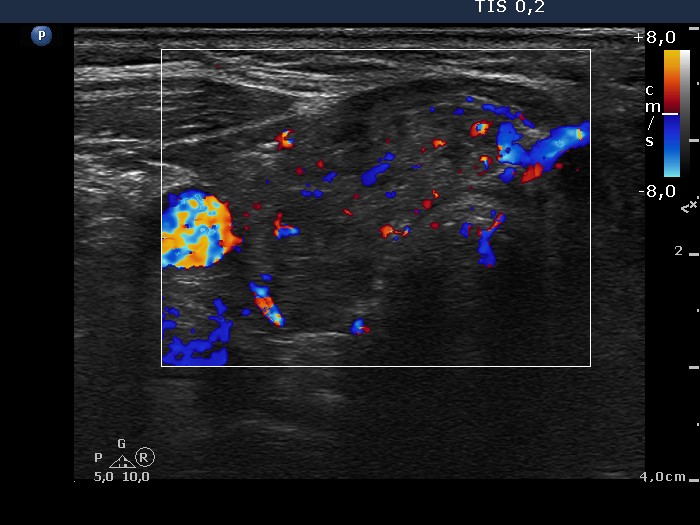

Ultrasonography: revealed hypoechogenic inhomogeneous thyroids. There was a hyperechogenic nodule in the left lobe. The nodule presented a halo sign and perinodular blood flow. It increased in size, therefore we performed aspiration cytology.Cytology: benign lesion.

It is worth comparing the numerous small echonormal lesions and the large nodule in the left thyroid. The former are part of the so-called pseudonodular form of Hashimoto's thyroiditis, while the true nodule was much larger. Pseudonodules are usually in the range of 5 to 15 mm in maximal diameter.

Most solitary nodules which are greater than 2 cm in maximal diameter, display a halo sign and perinodular blood flow are proved to be follicular tumor. This case belongs to the relatively rare exceptions.